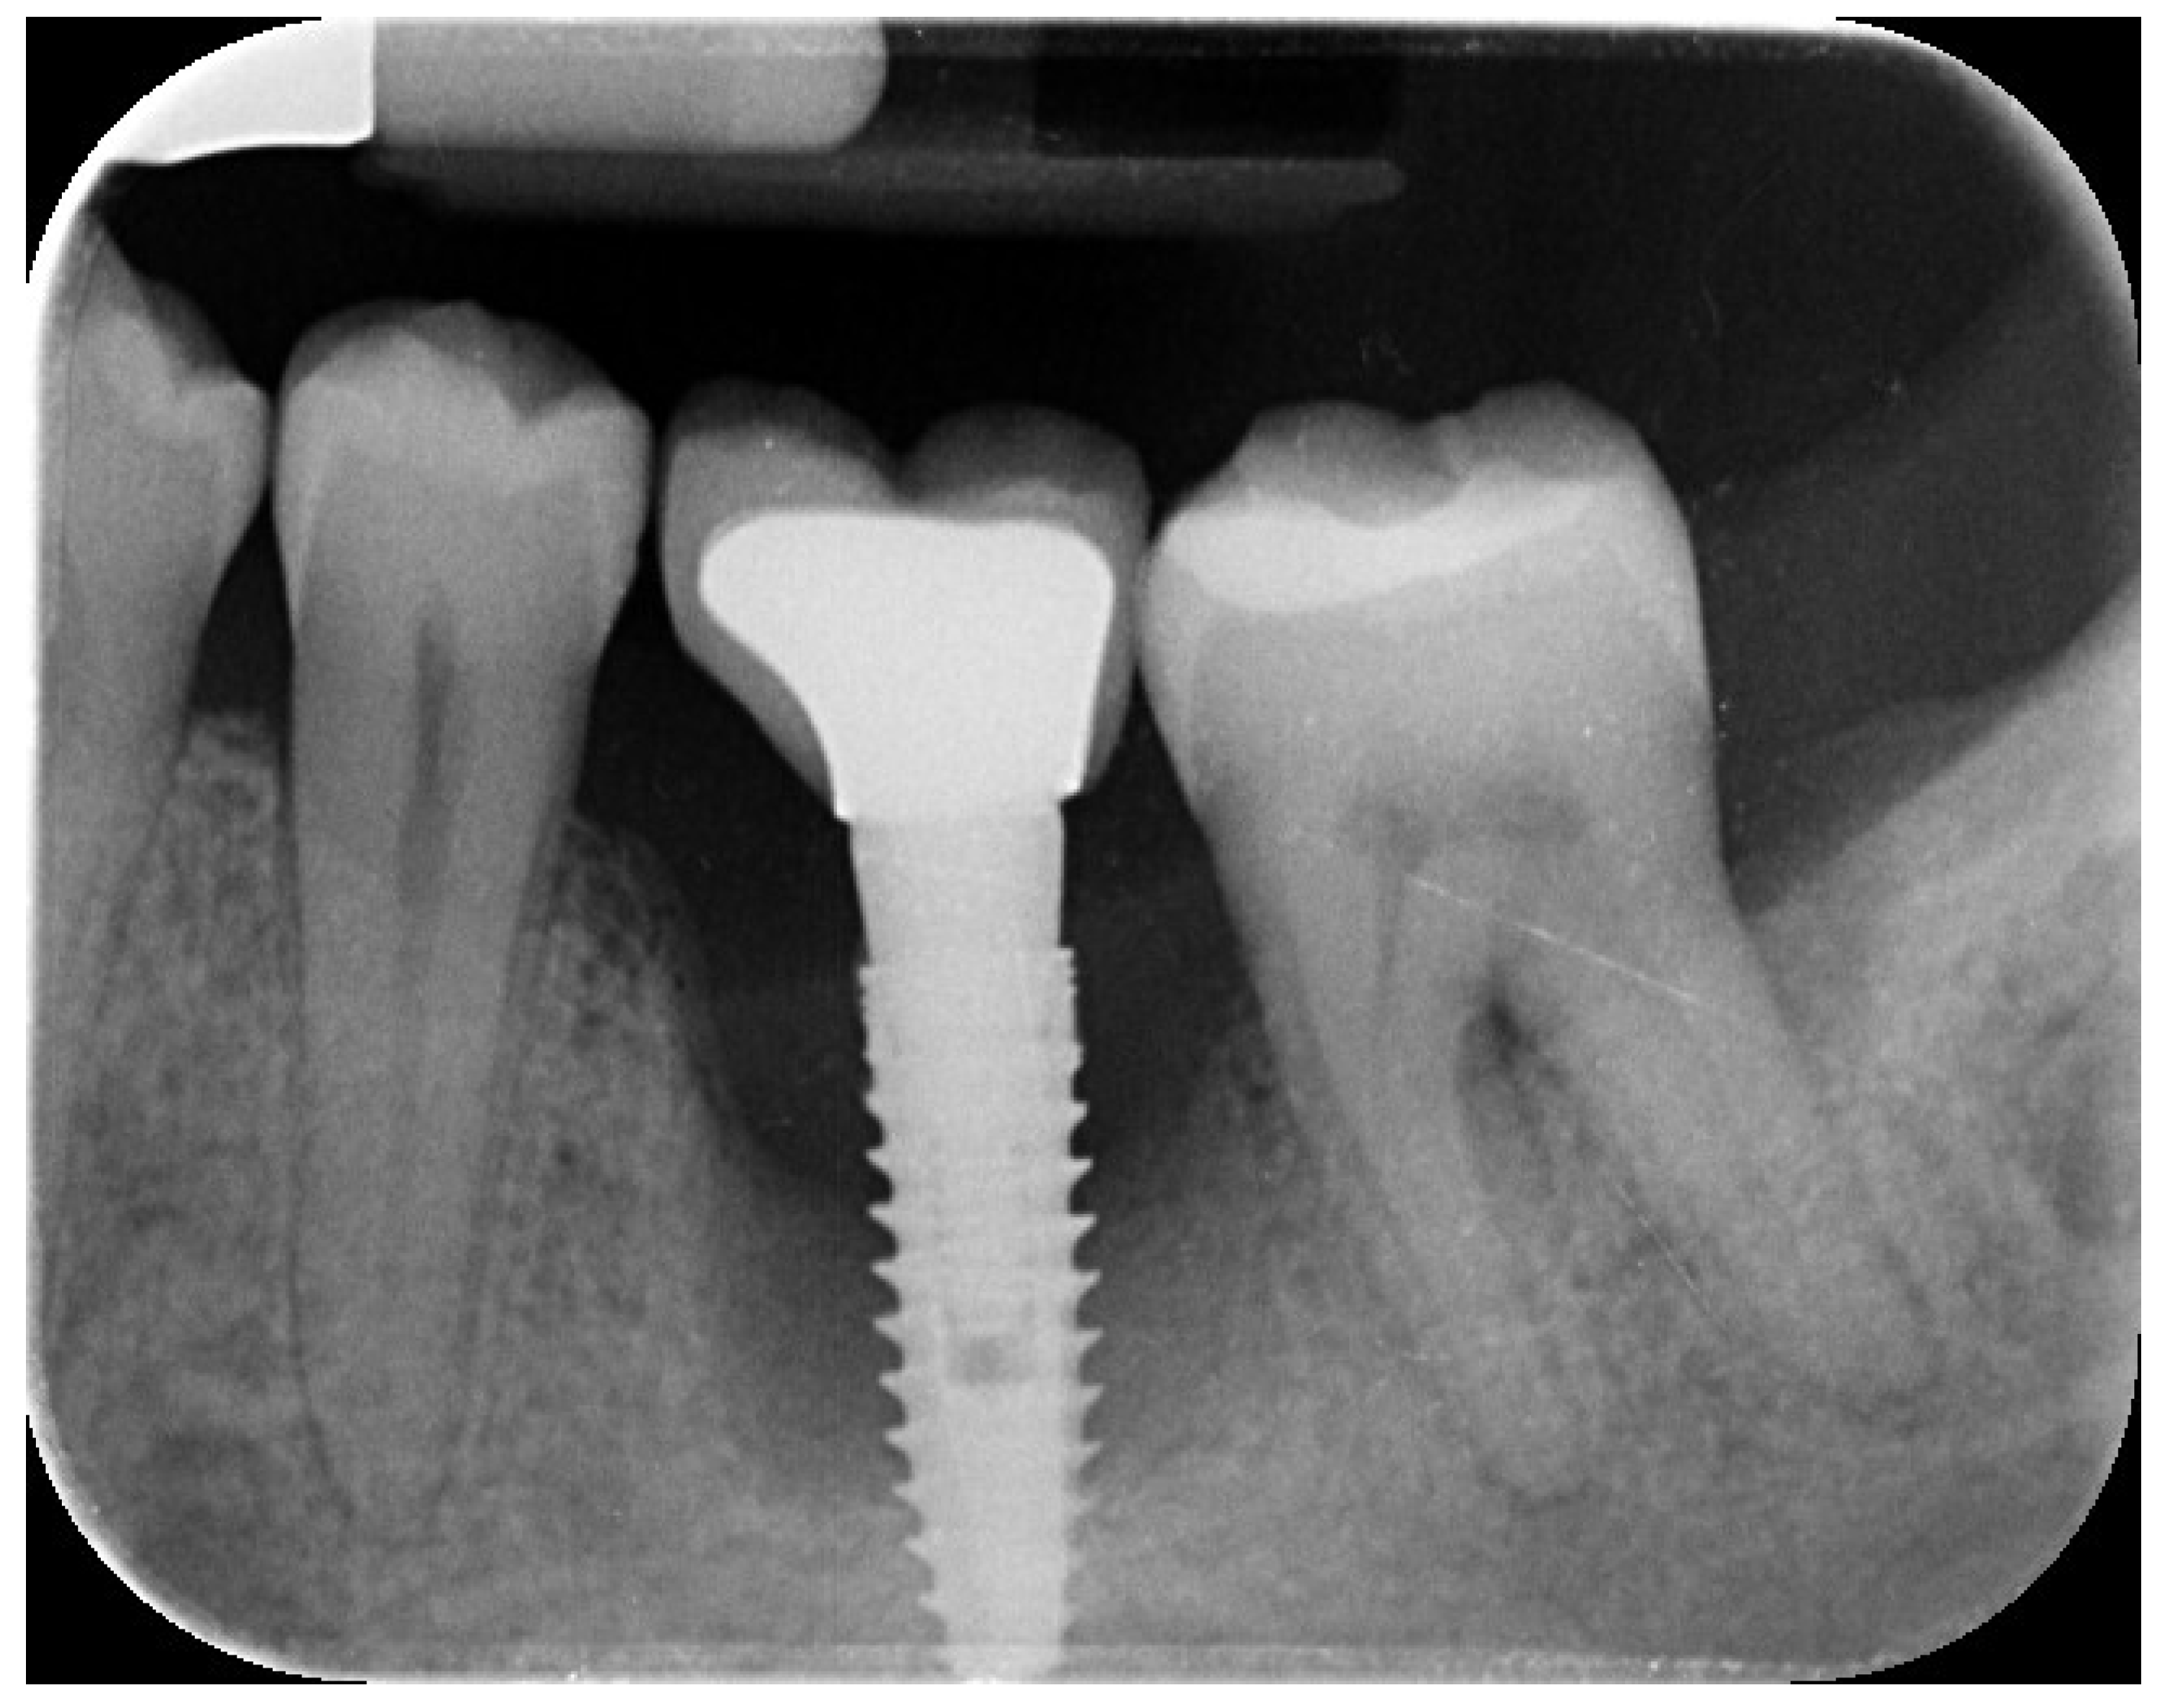

2. Case Summary